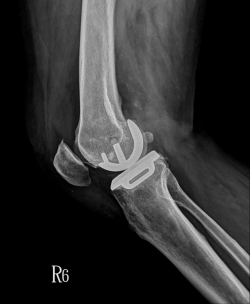

退休後的葉太太喜歡遊山玩水,但近幾個月來,常沒走幾步路就開始左膝疼痛,偶而蹲下時還會發出喀喀聲,到樂生療養院骨科檢查照X光後,被診斷為「退化性膝關節炎」。樂生療養院副院長、骨科主任周禮智指出,退化性膝關節炎的患者一般會感到關節疼痛,有時是間歇地隱隱作痛、活動受限,症狀惡化到最後可能會失去活動能力。 手術前病患常沒走幾步路就開始左膝疼痛,偶而蹲下時還會發出喀喀聲。圖:...... [閱讀更多]